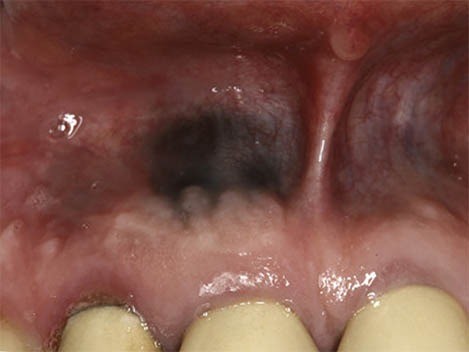

Amalgam Tattoo

An amalgam “tattoo” occurs when a silver filling is being placed and some of the metal filling material inadvertently becomes lodged in the gum tissue or cheek. It usually looks like a small, irregularly shaped dark blue discoloration. They may look strange when you brush your teeth, but these dots are perfectly harmless and require no treatment.